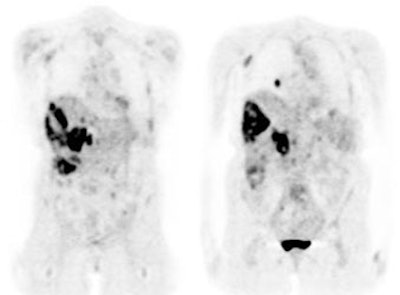

Diffuse lymphoma: In the case below, FDG PET imaging was performed prior to conventional imaging for patient staging. There is widespread tracer uptake within adenopathy in the neck, chest, abdomen, and pelvis. The spleen is enlarged and the intensity of FDG uptake is greater than the liver (SUV was 2.5) which is indicative of infiltrative splenic involvement. There was no evidence of osseous disease. (Click image to view rotating cine file) |

|